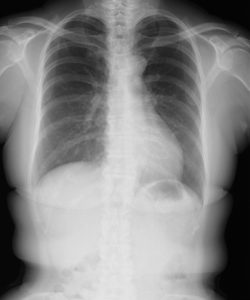

慢性閉塞性肺疾患(COPD)とは、従来、慢性気管支炎や肺気腫と呼ばれてきた病気の総称です。

長い間続く咳や痰、息切れが特徴の「肺の生活習慣病」です。主にタバコの煙や大気汚染などの影響で、呼吸をするための空気の通り道(気管支)が傷み、狭くなって、肺の機能が少しずつ低下していく病気です。

喫煙によってたばこの煙に含まれる有害物質を長期間吸い込むことで、肺に炎症が起こります。その炎症によって肺胞壁の破壊が進み、肺が異常に拡大する「肺気腫」が起きたり、空気の通り道である気道がむくんだり、気管支の中に痰が詰まったりします。